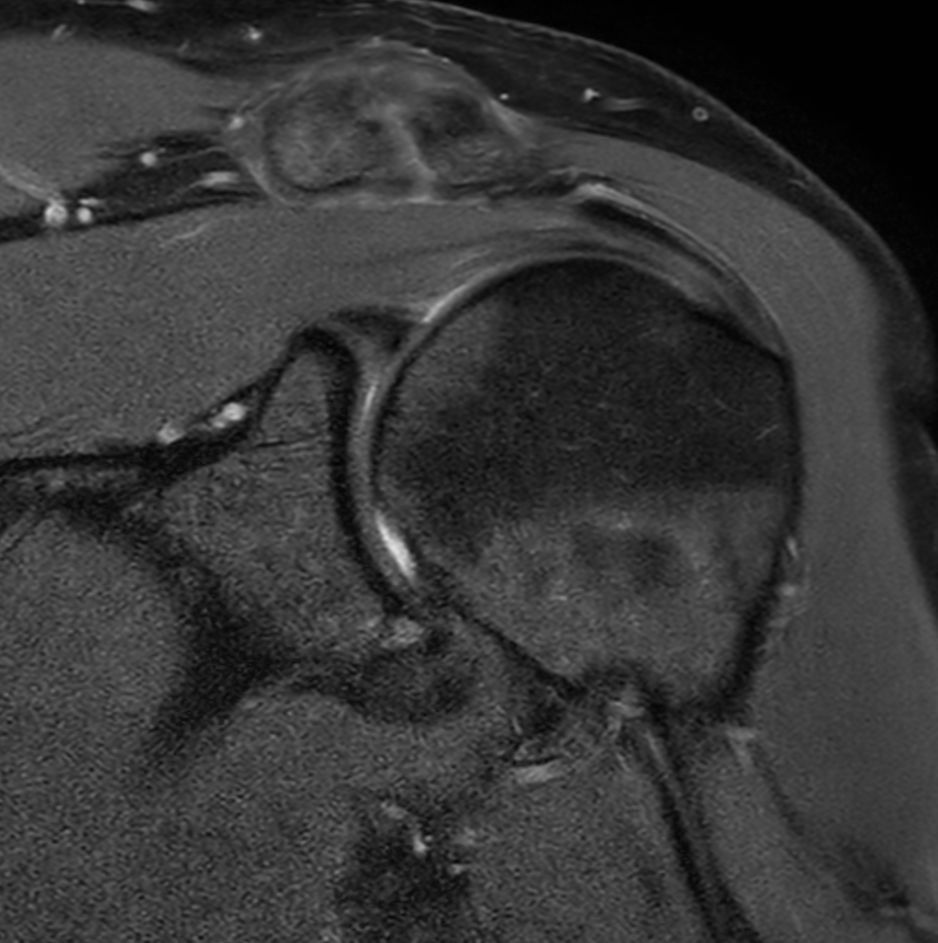

Shoulder with the dS Shoulder 16ch coil

University of Vermont Medical Center, Burlington, USA